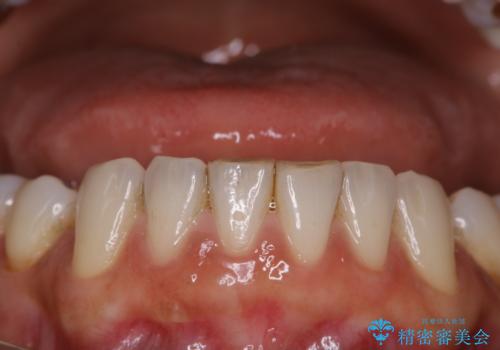

全体の総合的な治療前にPMTC

- 歯科がだいぶ久しぶりで、全額的な治療の前にクリーニングを希望されました。PMTC60分コースを行いました。

歯にステイン(着色)や歯石などが付着していると、汚れなのか虫歯なのかの判別が分かりにくく、正確な診断ができないことがあります。

そのため、治療前には専門的な機械や材料を使用したクリーニング(PMTC)をすることで、ご自身本来の歯の状態となります。より、精密な治療前を行うためには、治療前などにPMTCを行いお口の中の環境を綺麗にすることがおすすめです。